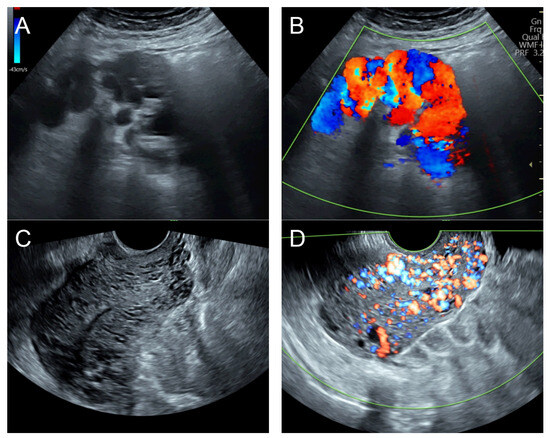

(A–C) Transabdominal grayscale ultrasound: cross-sectional, sagittal, and oblique scans of the uterus showed heterogeneous soft tissue content, like pieces of conceptive product in the uterine cavity; ill-defined endometrial–myometrial interface; hypoechoic lacunae varying in size in the non-specific tissue content, mainly localized at the left anterior wall. (D) Color flow mapping with a relatively high pulse repetition frequency of 3.2 kHz (applied to the same image (C)) showed hyper-vascularized lesions in the myometrium; multidirectional flow, mainly localized at the left anterior wall; and some cystic spaces of no flow, indicating lysed blood in the cavity. (E) Spectral Doppler ultrasound showed a high peak systolic velocity (approximately 60 cm/s). The sonographic diagnosis was uterine AVM. The main differential diagnoses were incomplete abortion (conceptive products) and gestational trophoblastic disease. (F) CTA during uterine embolization revealed hypervascularity and tortuous arterial anatomy enhancing a dilated vascular pouch overlying the endometrium of the uterus with feeding via the bilateral uterine arteries and draining via the internal iliac veins, confirming uterine AVM; low blood content in the uterine cavity without evidence of active contrast extravasation.